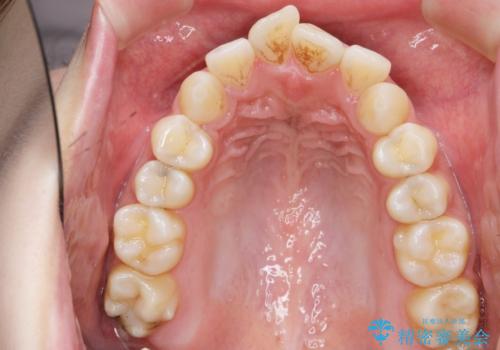

- 唇の閉じづらさと、前歯のがたつきの改善を希望され来院されました。

抜歯を行わなくてもなんとか並べられる歯並びですが、唇の閉じづらさをしっかりと改善するため抜歯を伴うマルチブラケット矯正を行うこととしました。

前歯をしっかりと後方に引いたことで、唇は閉じやすくなり、仕上がりに満足いただくことができました。